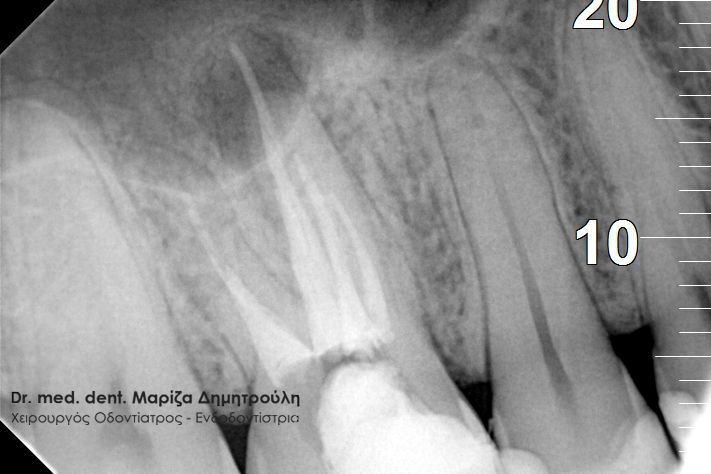

Περιστατικό – Επανάληψη απονεύρωσης δοντιού

Ο ασθενής παραπονείται για έναν μόνιμο πόνο στην περιοχή του αριστερού ιγμορείου. Ανέφερε οτι πριν χρόνια πραγματοποιήθηκε στον αριστερό γομφίο (τραπεζίτη) μία απονεύρωση. Μετά από καιρό εμφανίστηκαν τα συμπτώματα πόνου, χωρίς καμία βελτίωση. Μετά τον αποκλεισμό της ανάμειξης του ιγμορείου στη εμφάνιση των συμπτωμάτων ακολούθησε η κλινική και ακτινογραφική εξέταση του δοντιού. Η ακτινογραφία αποκάλυψε την ατελή απονεύρωση του δοντιού.

Μετά από συνεννόηση με τον ασθενή αποφασίστηκε η επανάληψη της ενδοδοντικής θεραπείας (απονεύρωσης). Ακολούθως έγινε τοποθέτηση του ελαστικού απομονωτήρα, η διάνοιξη του δοντιού και η αφαίρεση του παλιού εμφρακτικού υλικού από τις ρίζες.Επιπρόσθετα εντοπίστηκε και παρασκευάστηκε και 4ος ριζικός σωλήνας, ο οποίος δεν είχε επεξεργστεί στην πρώτη ενδοδοντική θεραπεία ( απονεύρωση ) του ασθενούς.

Διαπιστώθηκε η ενσβεστίωση 2 ριζικών σωλήνων του δοντιού (ριζών), κάτι που δεν επέτρεψε την επεξεργασία του δοντιού σε όλο το μήκος αυτών των ριζών. Παρολ΄ αυτά μετά τη δεύτερη συνεδρία ο ασθενής ανέφερε την ανακούφιση και την εξάλειψη των συμπτωμάτων, που τον ταλαιπωρούσαν τα τελευταία χρόνια.

Εφόσον το δόντι ήταν ασυμπτωματικό και ο ασθενής δεν αισθανόταν πλέον πόνο ολοκληρώθηκε η διαδικασία της απονεύρωσης με τη χρήση των μηχανοκίνητων εργαλείων και την τελική έμφραξη των ριζών του δοντιού με νέο εμφρακτικό υλικό.

ΠΡΙΝ

ΜΕΤΑ